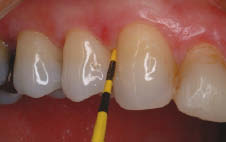

Figure 4-A very severe case of early childhood caries in a young child. Note the paruli present on the buccal gingiva of teeth 52 and 63. All maxillary anterior teeth are unrestorable and require extraction.